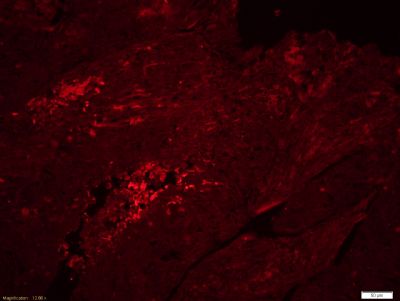

Fibrinogen beta chain,纤维蛋白原β链抗体产品应用WB=1:100-500 ELISA=1:500-1000 IHC-P=1:100-500 IHC-F=1:100-500 ICC=1:100-500 IF=1:100-500 (石蜡切片需做抗原修复)